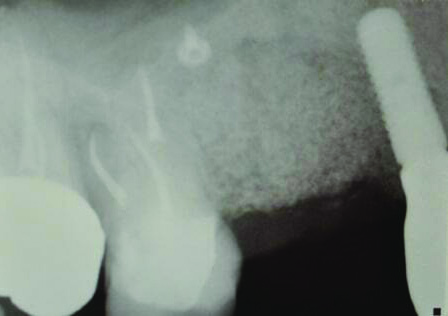

Fig 12. Case 2: Immediate postoperative radiograph. Note the tack securing the collagen membrane (upper left portion of the image).

Figure 12

The patient in case 2 received a crestal incision with full-thickness flap elevation, then tooth No. 5 was extracted (Figure 9). Implant debridement followed the same protocol used in case 1. FDBA was mixed with a small amount of doxycycline and placed around the implant (Figure 10). A resorbable collagen membrane (not pictured) was secured with a tack. Primary closure was achieved with expanded polytetrafluoroethylene (ePTFE) sutures (Figure 11). An immediate post-surgical radiograph showed bone fill and the tack (Figure 12).

The 12-month and 7-year follow-ups for case 2 showed similar improvements with normal soft-tissue healing and bone fill and normal pocket depths at 12 months (Figure 15 and Figure 16) and 7 years post-treatment (Figure 17 and Figure 18) (Table 1).